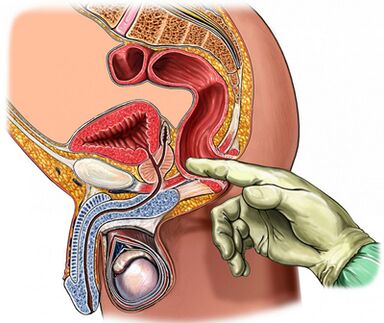

- Un complexe de méthodes physiques (examen rectal au doigt de la prostate).

Palpation de la glande de la prostate

La palpation de la prostate, qui augmente pendant la période d'exacerbation et d'acceptation de la filiale du processus inflammatoire, est de la plus grande importance lors du diagnostic de la maladie. Dans la prostatite chronique, l'aggravation du fer est gonflée et douloureuse.

La densité de la consommation d'organes peut varier: les zones d'adoucissement et de compression sont analysées, les zones occidentales sont déterminées. Dans le cas de la palpation, il est possible d'évaluer la forme de la glande, l'état de la tubérel de graines et des tissus environnants.

Le processus d'examen des doigts transrectaux est combiné avec la saisie de la glande. Parfois, il est nécessaire d'obtenir un secret séparément de toute proportion.